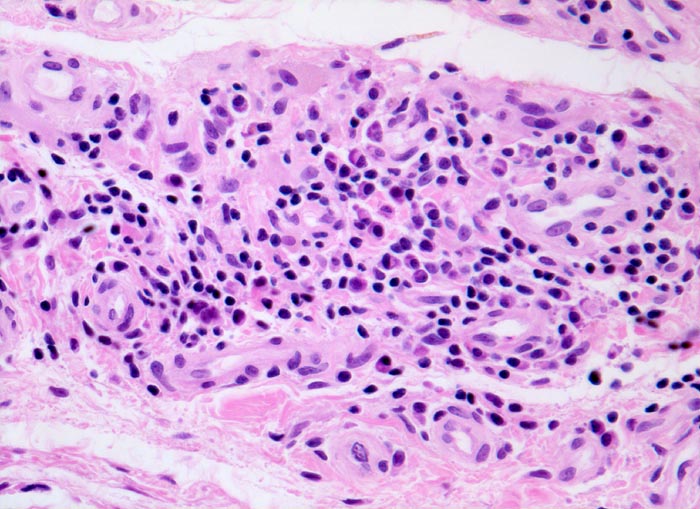

PathoPic ID 4776 - Synovialitis bei chronischer Polyarthritis

Synovialitis bei chronischer Polyarthritis

Systemerkrankung/Immunpathologie

Synovialis

Knochen, Knorpel, Gelenke

Lymphoplasmazelluläres Entzündungsinfiltrat im Stroma. Die Plasmazellen sind gut erkennbar an der

perinukleären Zytoplasmaaufhellung.

Bekannte seropositive chronische Polyarthritis.

Der Nachweis von Plasmazellen ist typisch, aber nicht beweisend für eine chronische Polyarthritis.

Histologie

200